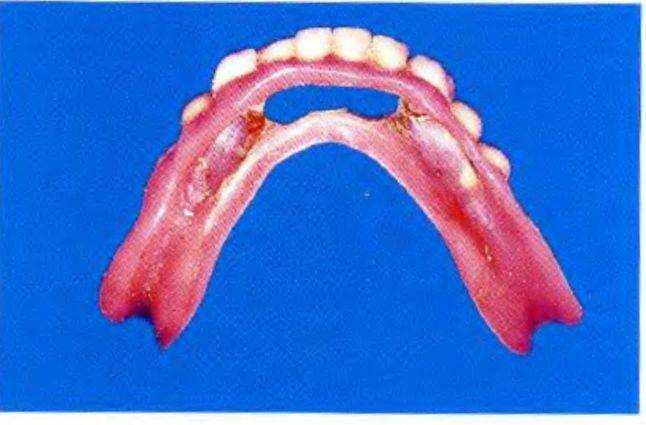

После этого протез перебазировали с помощью самоотверждаемой пластмассы и отполимеризовали балку внутри протеза, закрыв поднутрения красными резиновыми кольцами (см. рис. 1-9bb). На рис. с 1-9gg по 1-9ii продемонстрированы различные поверхности подготовленного протеза, который надежно фиксировался в полости рта пациента (рис. 1 -9jj).

Рис. 1-9gg. Основание протеза нижней челюсти с полимеризованной в его основании балкой.

Рис. 1-9hh. Вид основания съемного протеза. Четко визуализируются направляющие колпачки балки

Рис. 1-9ii. Готовый отполированный протез нижней челюсти.